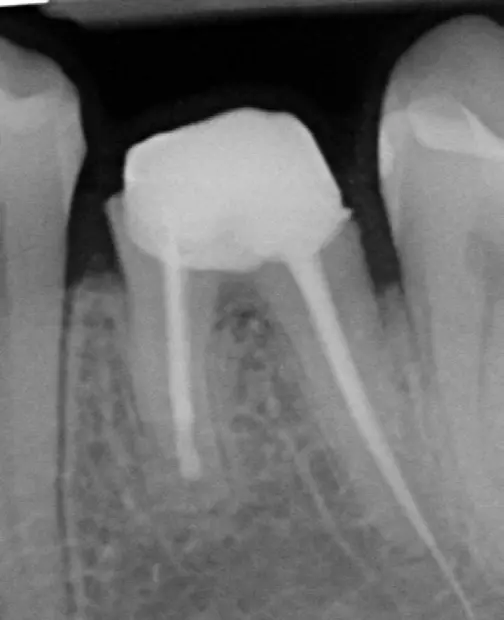

Katafuchi et al. [10] konnten in einer klinischen, röntgenologischen Studie an 83 Patienten mit 168 Implantaten eindrucksvoll einen Zusammenhang von Emergenzwinkel und Emergenzprofil zur Periimplantitisprävalenz herstellen. Die 168 Implantate teilten sich wie folgt auf: 101 Implantate in 59 Patienten waren Bone-Level und 67 Implantate bei 27 Patienten Tissue-Level Implantate. 22,8% der Bone-Level Implantate waren von Periimplantitis betroffen, hiergegen standen nur 7,5% der Tissue-Level Implantate.

Bone-Level Implantate zeigten ein signifikant höheres Periimplantitisrisiko, wenn der Emergenzwinkel >30° betrug, im Vergleich zu den Bone-Level Implantaten, deren Abutment ein Emergenzwinkel von <30° aufwies (31,3% zu 15,1%). Bei Tissue-Level Implantaten konnte dieser Zusammenhang nicht nachgewiesen werden.

Wenn zusätzlich zu dem Emergenzwinkel auch noch das Emergenzprofil in die Analyse einbezogen wurde, zeigte sich bei einem Emergenzwinkel >30° in Kombination mit einem konvexen Emergenzprofil (Abb. 3) auf mindestens einer interproximalen Seite eine signifikante Erhöhung der Periimplantitisprävalenz von 37,8% (p=0,003).

Auch diese signifikante Erhöhung des Periimplantitisrisikos bezieht sich auf Bone-Level Implantate, nicht aber auf Tissue-Level Implantate. Es scheint, dass die reduzierte Hygienefähigkeit und die damit verbundene erhöhte Plaqueakkumulation für die erhöhte Periimplantitisprävalenz von Implantaten, die mit Abutments mit weitem Emergenzwinkel und konvexem Emergenzprofil versorgt sind, verantwortlich sind [11].